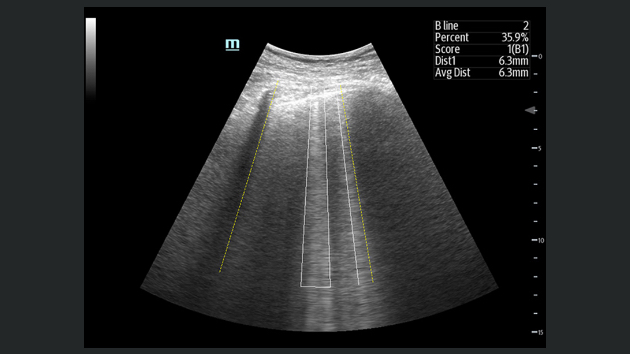

The TE9 Ultrasound System is designed to expand imaging capabilities across point-of-care environments including anaesthesia, emergency, and critical care.

A large clear touchscreen, superior imaging and intelligent diagnostic tools allow the TE9 to support clinical efficiency and diagnostic confidence in high acuity settings. Its compatibility with a wide range of transducers means it can easily adapt to meet point-of-care needs and support a wide range of procedures and diagnostics.

Images